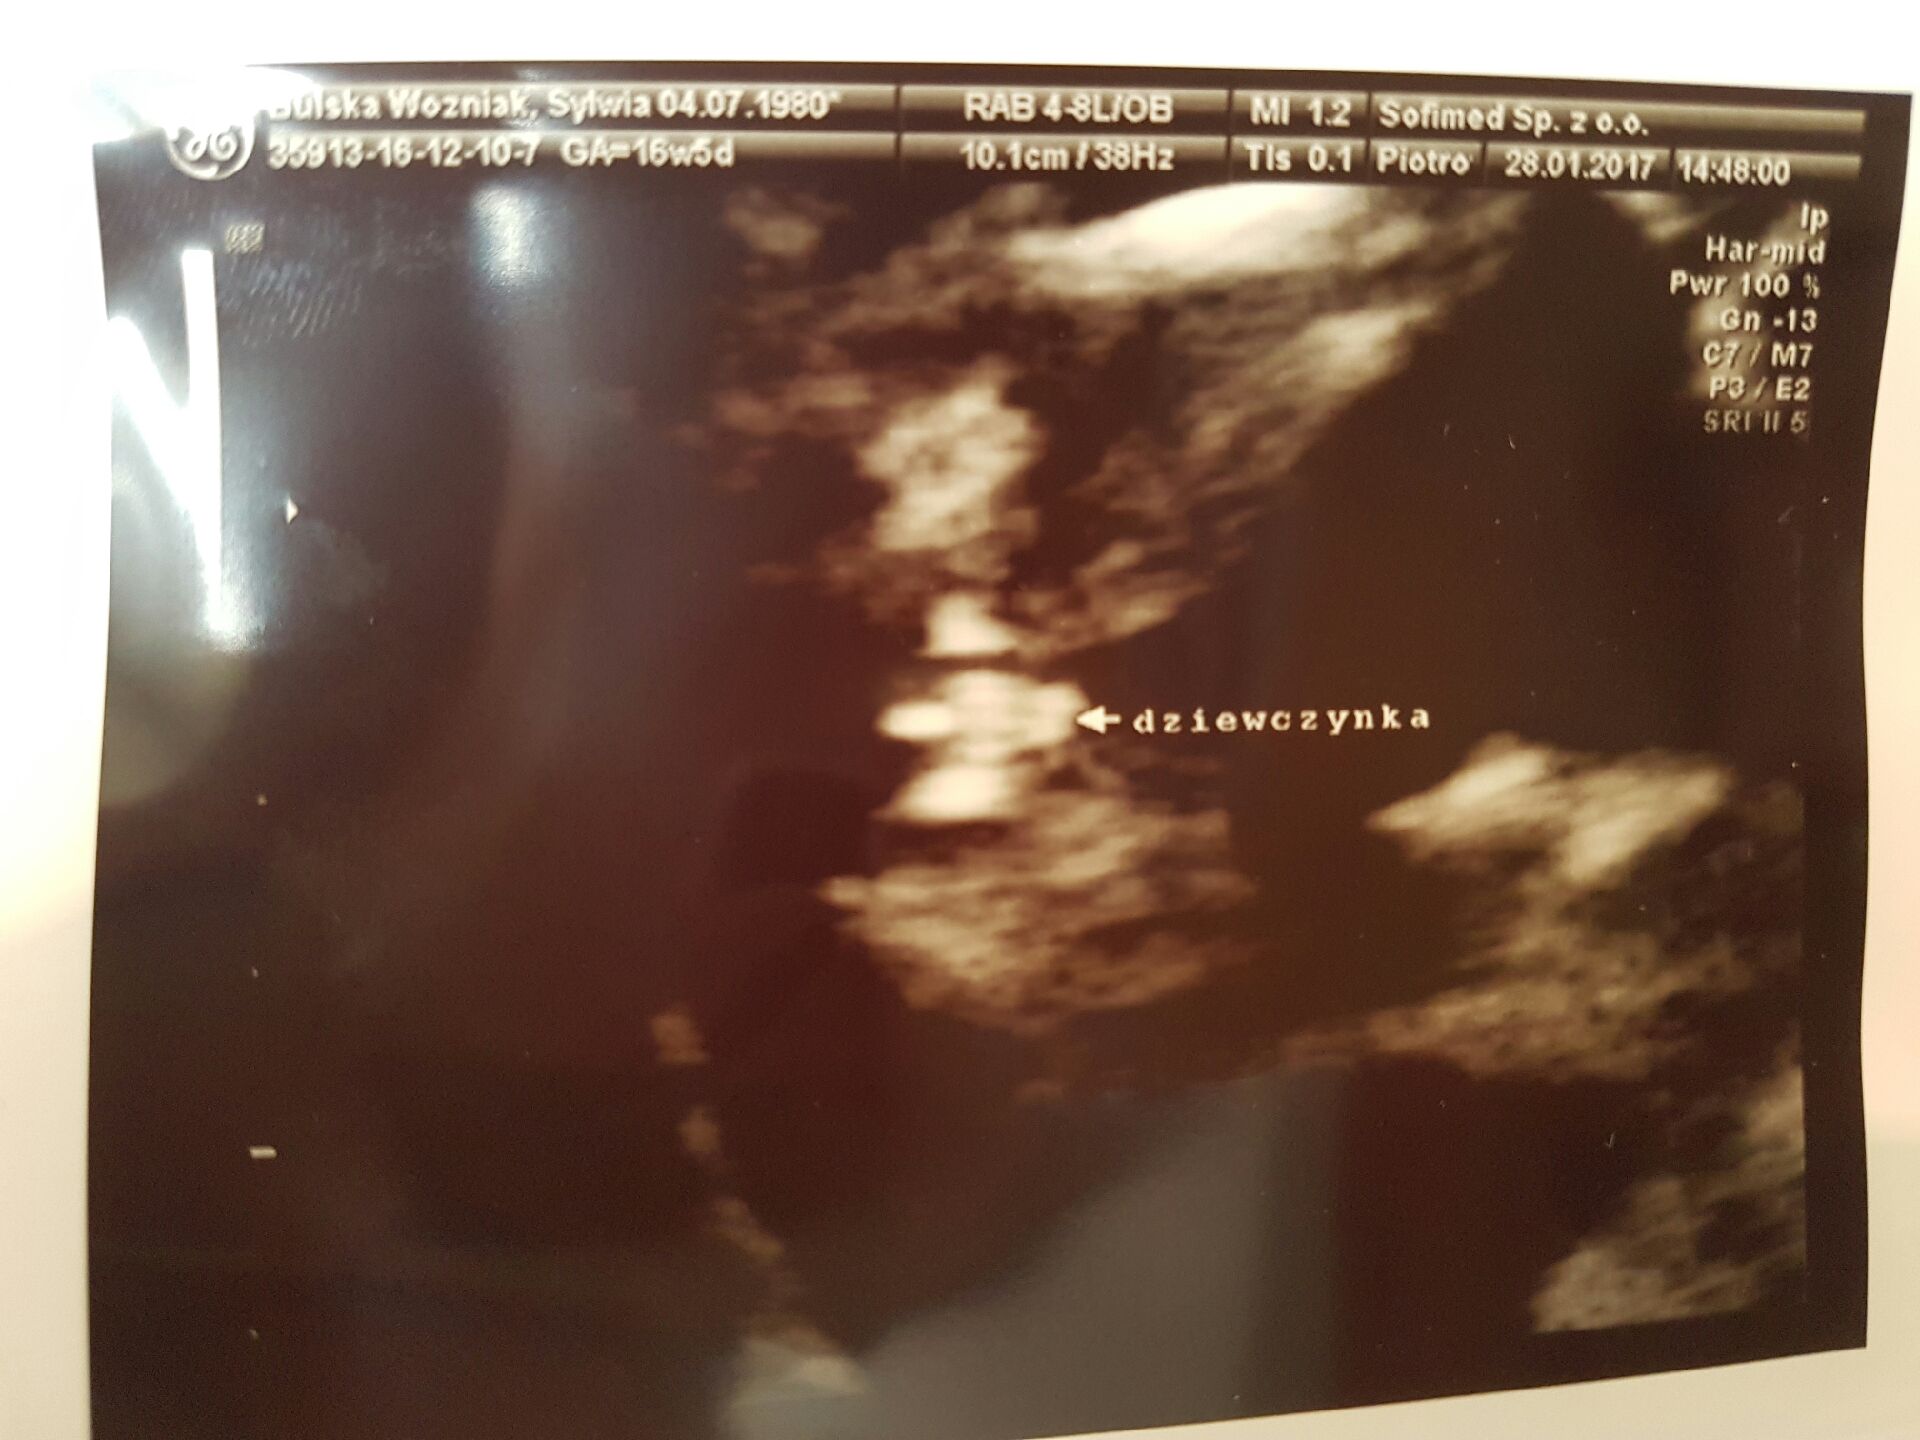

Moje Kochane, znowu mam dużo do nadrabiania, a wczoraj przecież pisałam, ale chcę Wam tylko powiedzieć, że... chyba u nas Zosia! Lekarz powiedział, że 100% nie ma, ale możliwe to, żeby w 17 tygodniu wyrosły jeszcze jajka? Zanim powiedział, co to, ja już widziałam, że dziewczynka! Wyszłam tak rozemocjonowana, że głowa mnie z tego wszystkiego zaczęła boleć ;-)

Moje Kochane, znowu mam dużo do nadrabiania, a wczoraj przecież pisałam, ale chcę Wam tylko powiedzieć, że... chyba u nas Zosia! Lekarz powiedział, że 100% nie ma, ale możliwe to, żeby w 17 tygodniu wyrosły jeszcze jajka? Zanim powiedział, co to, ja już widziałam, że dziewczynka! Wyszłam tak rozemocjonowana, że głowa mnie z tego wszystkiego zaczęła boleć ;-)Zobacz załącznik 793237

Kochana ale tam widać siusiaczka